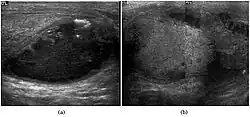

Fig. 6. Mature cystic teratoma. (a) Composite Image. Mature cystic teratoma in a 29-year-old man. Longitudinal sonography image of the right testis shows a multilocular cystic mass. (b) Mature cystic teratoma in a 6-year-old boy. Longitudinal sonography of the right testis shows a cystic mass containing calcification with no obvious acoustic shadow.